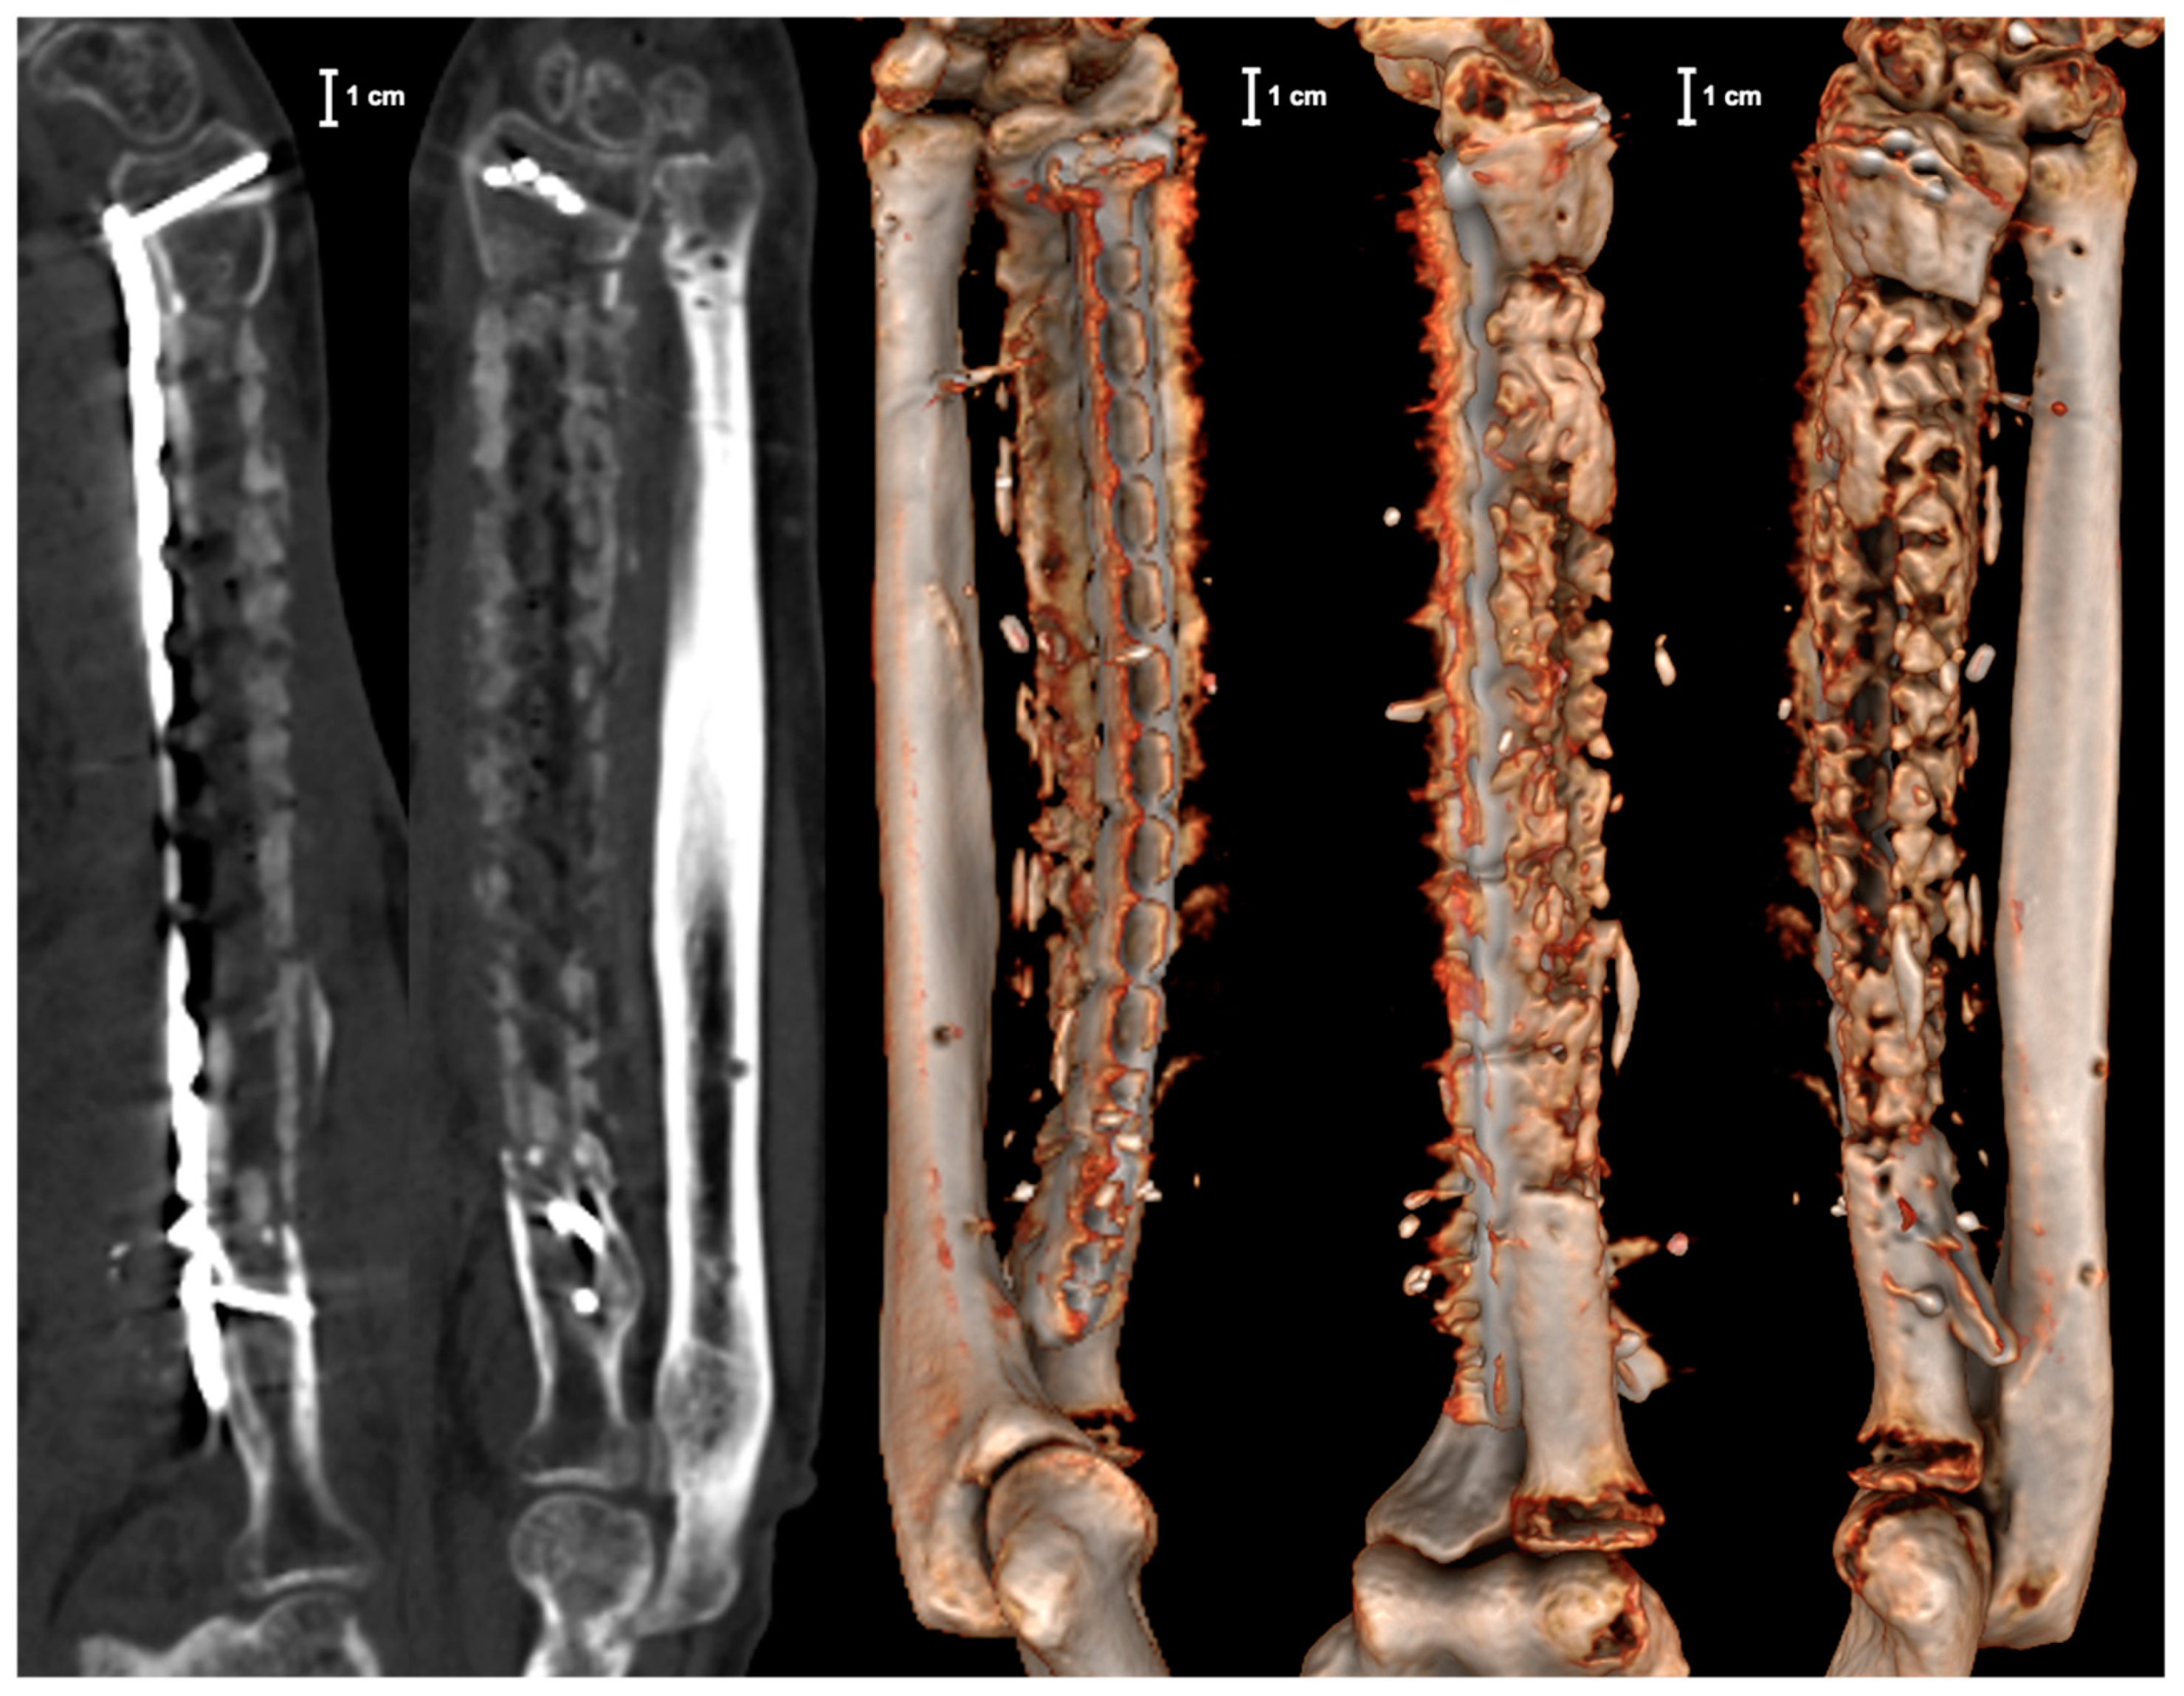

2. Case Report